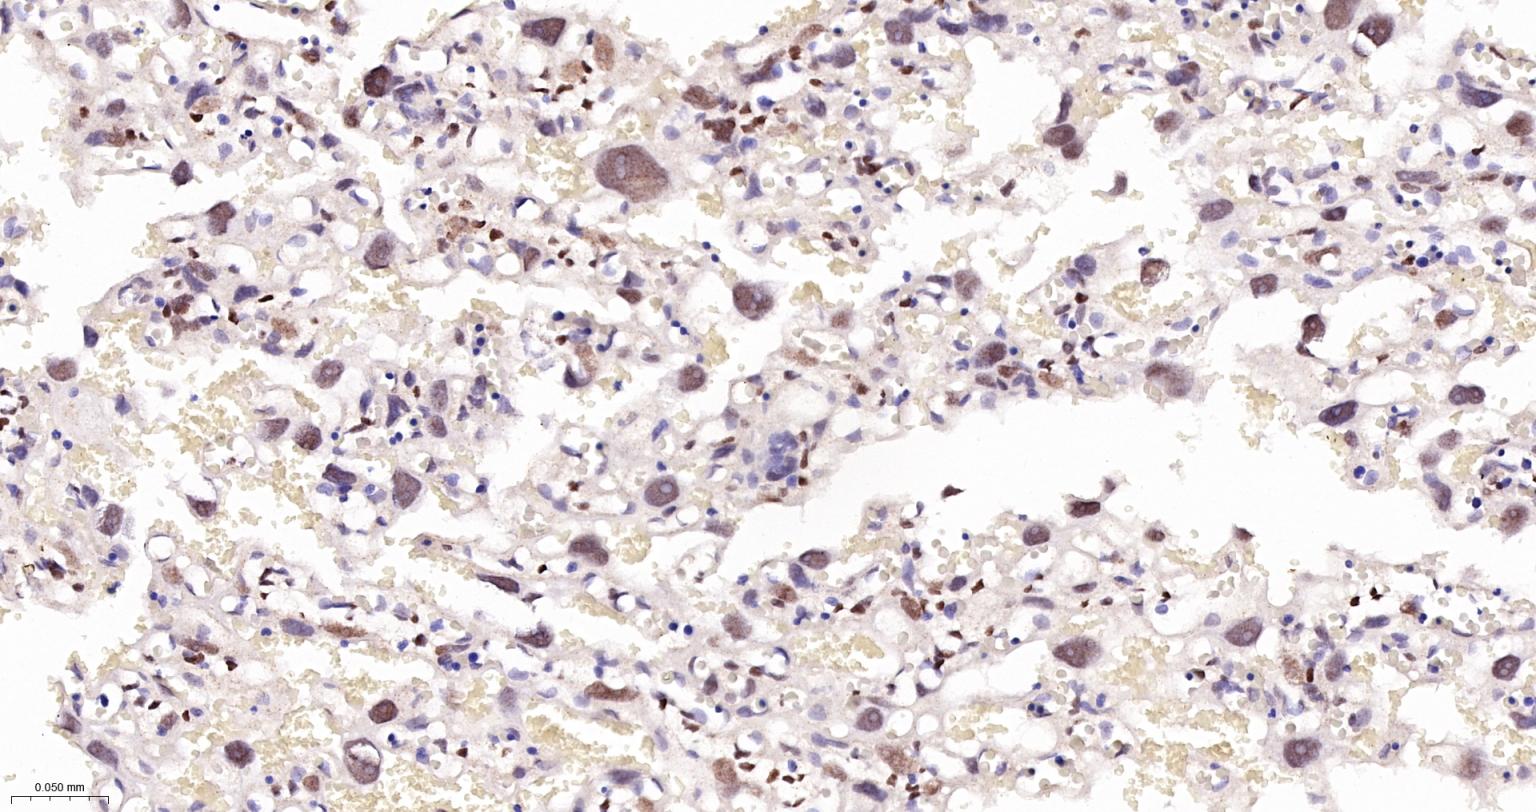

Paraformaldehyde-fixed, paraffin embedded Human Lung Cancer; Antigen retrieval by boiling in sodium citrate buffer (pH6.0) for 15 min; The section was incubated with TEAD1 Monoclonal Antibody, Unconjugated (bsm-63274R) at 1:200 overnight at 4°C, followed by conjugation to the bs-0295G-HRP and DAB (C-0010) staining.